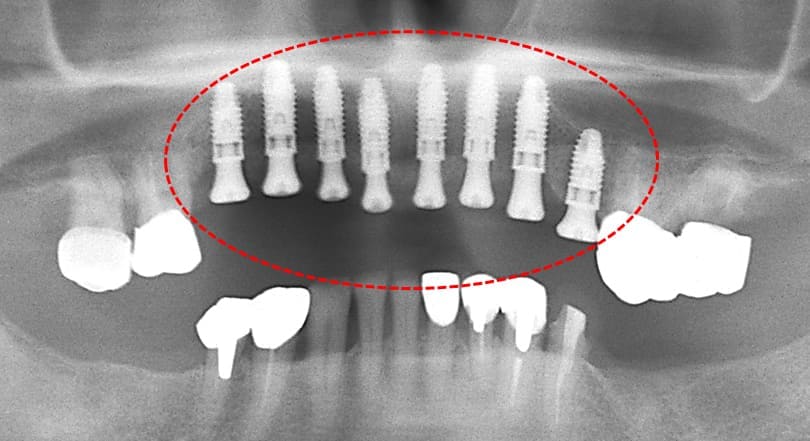

初診時のパノラマX-P所見

#17,15,14,13,23,24,27,36,44,45,46,47 が残根状態で温存は不可能であり、患者さん自身もそれを自覚しておられた。

初診時のパノラマXP所見

上顎前歯を含む第2小臼歯から対側の第2小臼歯までの10本のブリッジが脱離しそれを支えていた歯自体が保存できない状態であった。また下顎の臼歯部も欠損しており、このことで垂直的な咬合の安定が得られず前歯に負担がかかる崩壊脱離したと考えられる。

#15,14,21,22,23,27,36が残根状態で温存は不可能であり、患者さん自身もそれを自覚しておられた。

上顎にインプラント8本を埋入した術後のパノラマXP所見:上顎骨に対するインプラントの長さに関しては12mm-10mmが適切であり前歯部では12mmを小臼歯部では10mmを選択している。また左下のブリッジに関しては温存できなかった第2大臼歯が抜去されている。